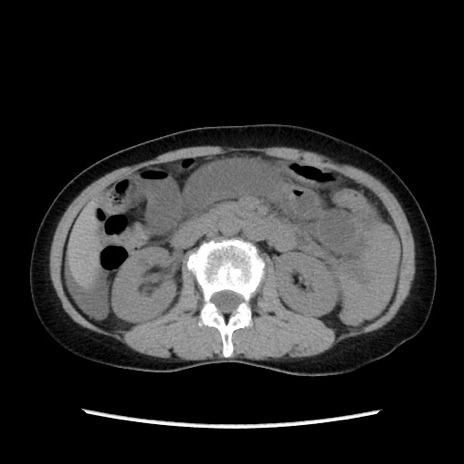

症例32(横断像)

【症例】40歳代 女性

【主訴】上腹部痛、嘔気・嘔吐

【現病歴】約9時間前頃から急に上腹部痛、嘔気、嘔吐が出現。改善しないため救急要請。

【既往歴】子宮頚癌(広汎子宮全摘術、放射線療法)、腸閉塞

【身体所見】腹部:平坦、軟、腸雑音亢進、上腹部を中心に腹部全体に圧痛あり。

【データ】WBC 8400、CRP 0.03